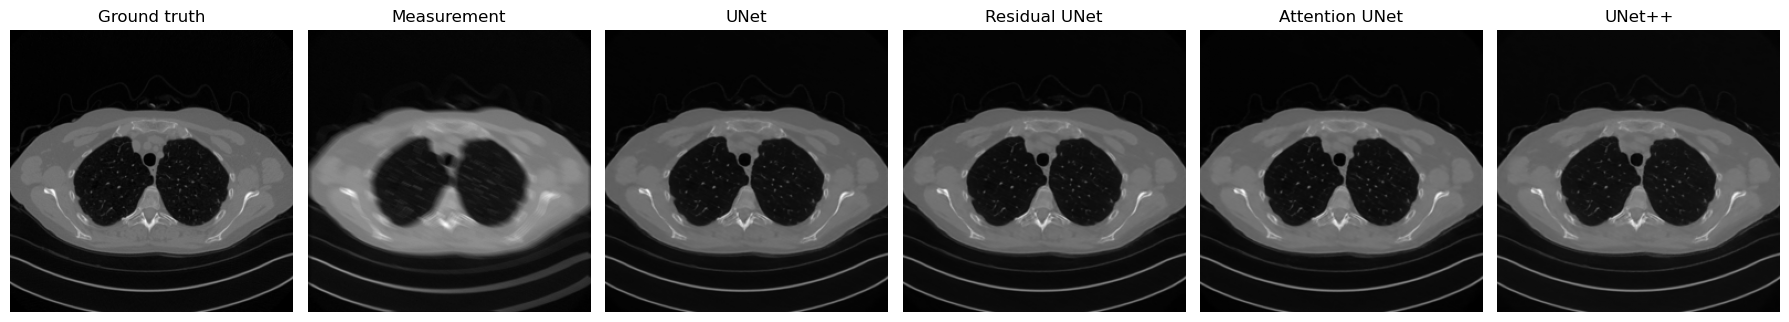

Comparing the Variants on the Same Corrupted Image#

To conclude the section, we now reconstruct the same corrupted test image with all four architectures: the plain UNet, the Residual UNet, the Attention UNet, and UNet++. This comparison is useful because it isolates the architectural choice while keeping the input corruption fixed.

Pedagogically, this final step matters a lot. Students should not leave the discussion with the impression that these variants are only abstract design ideas. The point is to see that small changes in block design, skip selection, or feature fusion can lead to visibly different reconstruction behavior even when the overall encoder-decoder structure remains the same.

UNet | MSE = 0.000075

Residual UNet | MSE = 0.000083

Attention UNet | MSE = 0.000087

UNet++ | MSE = 0.000080